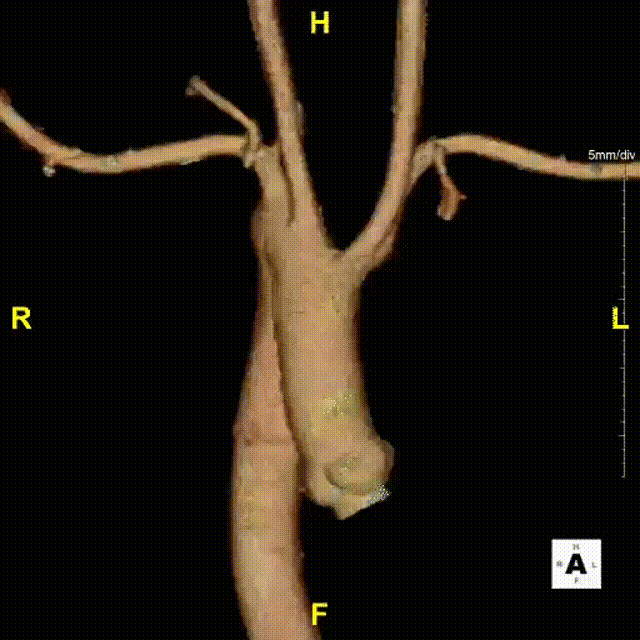

术前CTA提示右弓右降、合并Kommerell憩室,弓上各分支镜像分布。测量如下:

右弓右降,弓型陡峭,角度在40°左右

Kommerell憩室,38mm*30mm